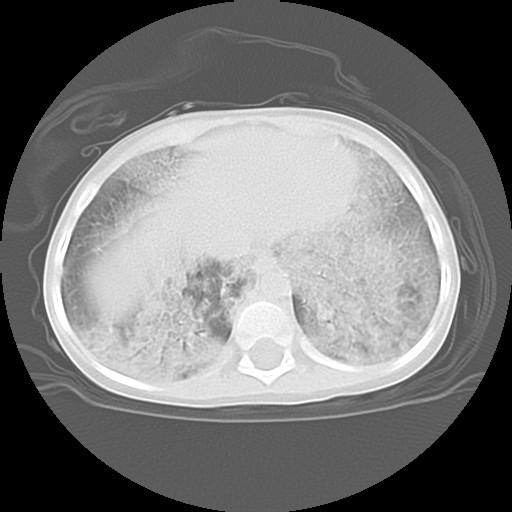

![]() Figure 4a |

![]() Figure 4b |

![]() Figure 4c |